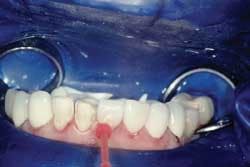

Rubber dam use is critical on mandibular teeth to isolate the lip and tongue and control moisture. Vanilla Bite (Discus Dental) was used to seal the lingual area (Fig. 1). Rubber dam use is also recommended for maxillary teeth. The preparations were cleansed with ConsepsisScrub (Ultradent) and a prophy cup (Fig. 2).

Gingibraid Oe (Van R) retraction cord was placed where the margins were at or below the crest of tissue.

A Vivastick (Ivoclar Vivadent) often is used to transport mandibular veneers into place (Fig. 5).